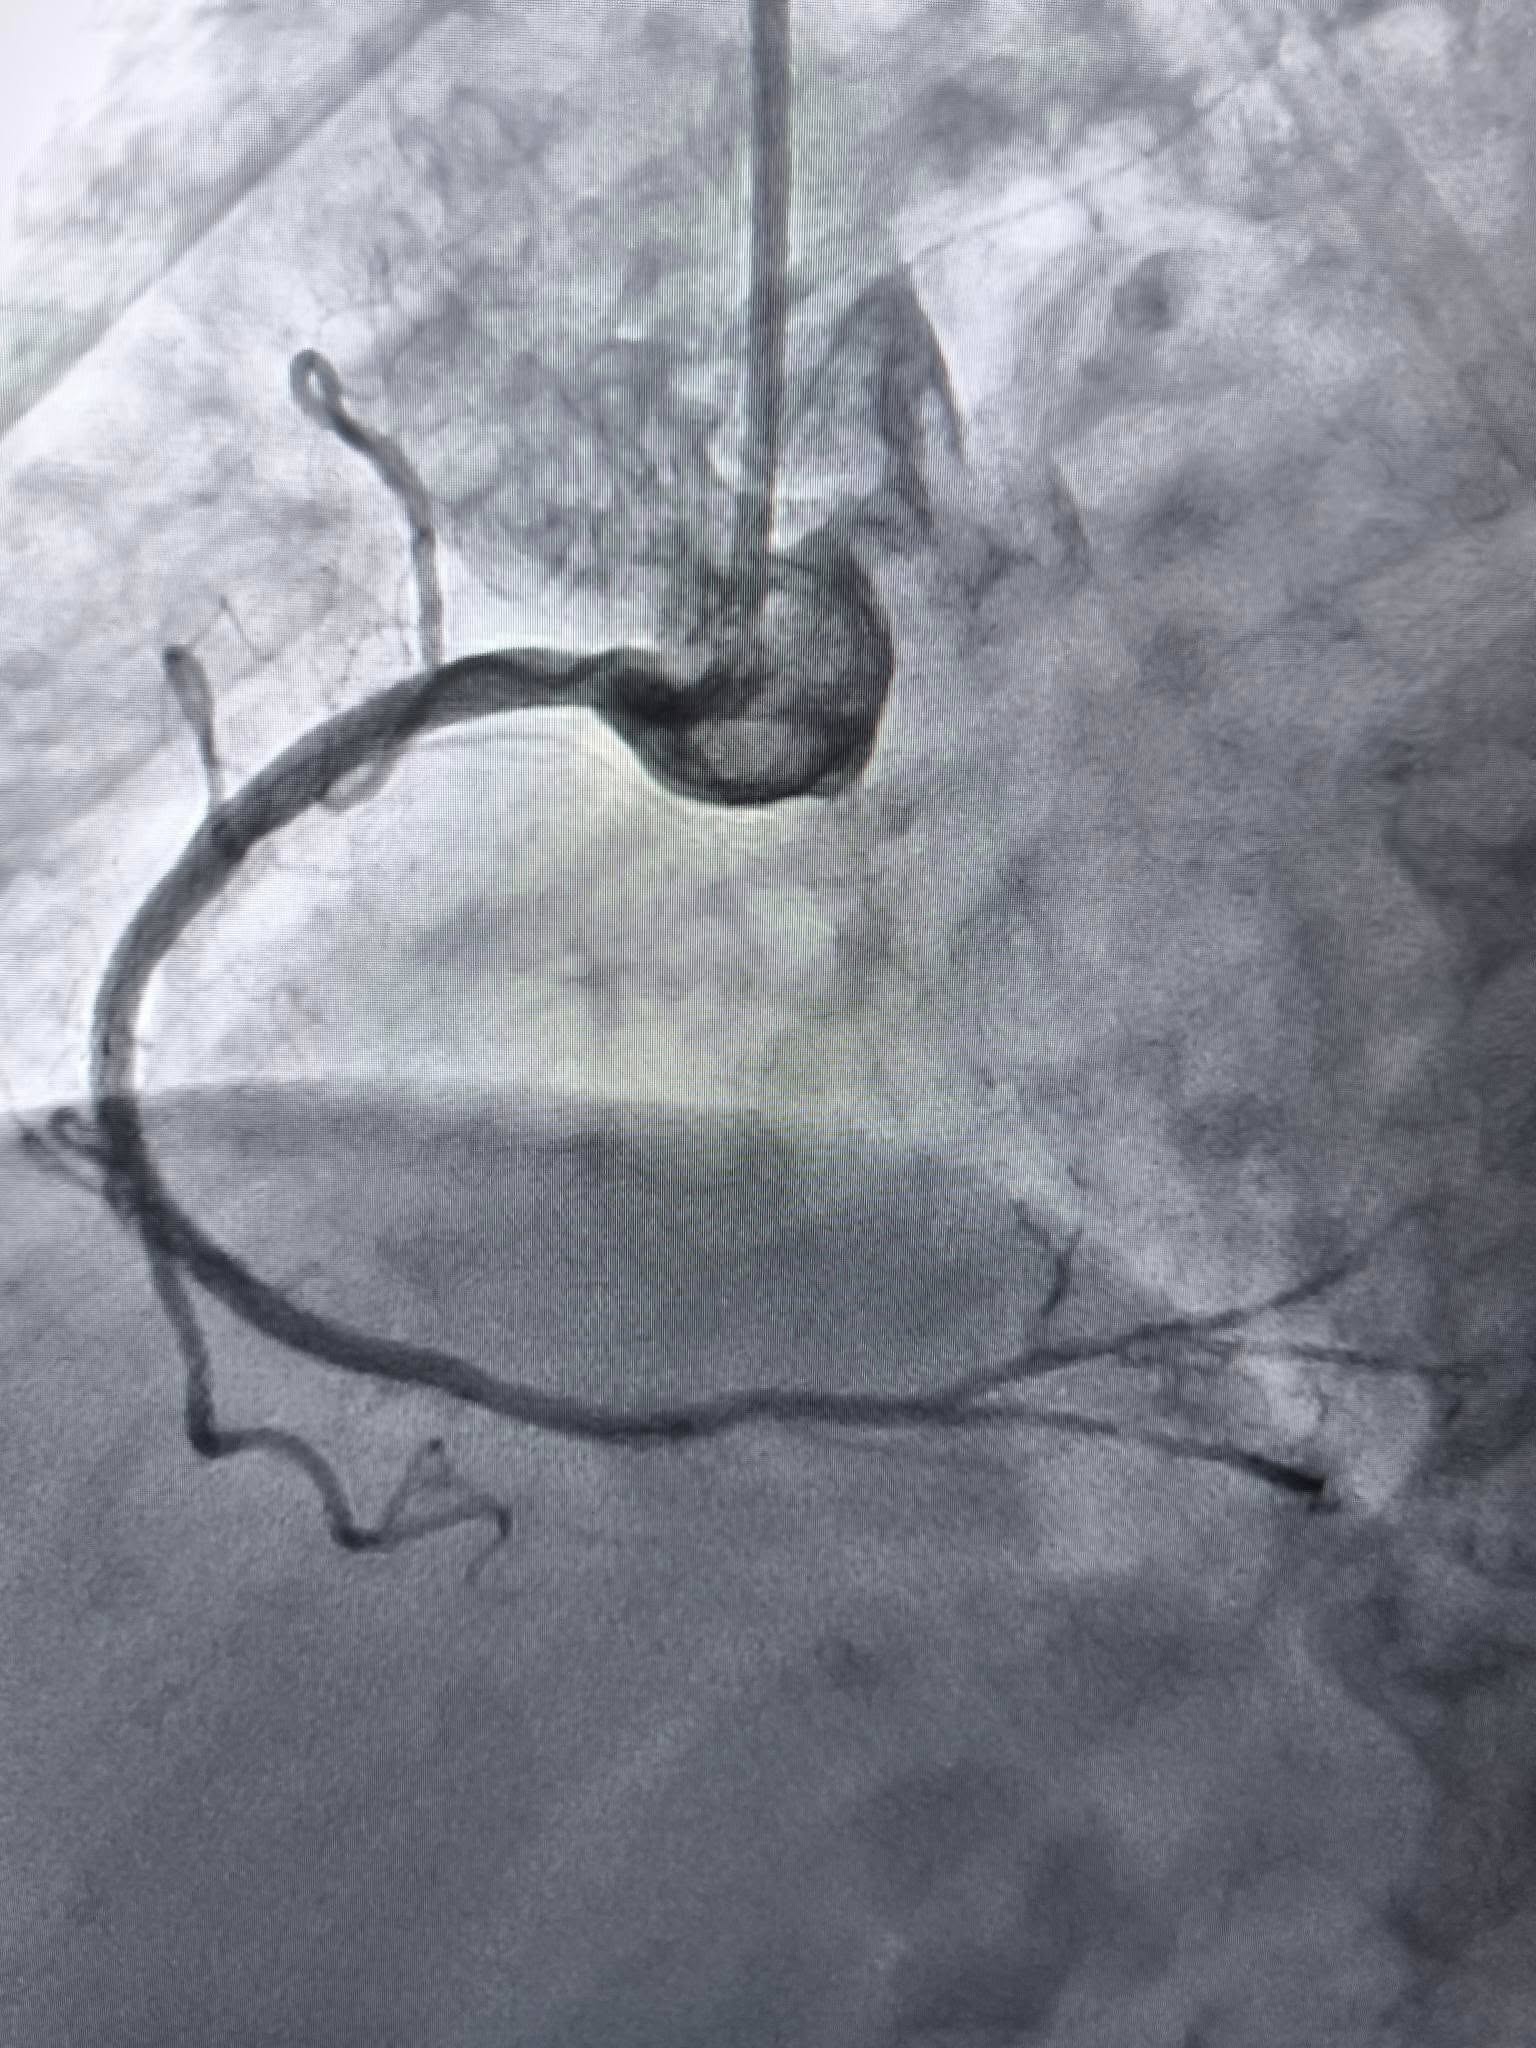

За словами завідувача відділенням інтервенційної радіології, кардіології та реперфузійної терапії Богдана Маслія, у пацієнтки діагностували значне звуження правої коронарної артерії. Розширити її традиційним способом – шляхом роздування балона, не вдалося, навіть із використанням високого тиску до 25 атмосфер (це приблизно у десять разів більше, ніж тиск в автомобільному колесі).

У таких ситуаціях на допомогу приходить ротаблятор – спеціальний пристрій із буром, покритим діамантовим напиленням. Він дозволяє «модифікувати» кальциновану атеросклеротичну бляшку, фактично шліфуючи її та відновлюючи можливість для подальшого стентування судини. Саме таким методом лікарям вдалося ліквідувати перешкоду в артерії та успішно імплантувати стенти.